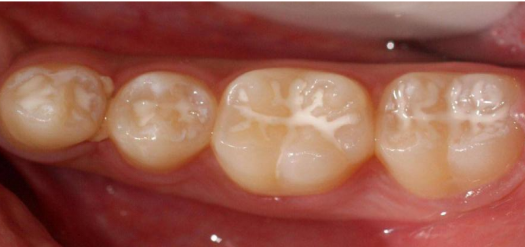

窝沟封闭是针对牙齿发育时候的儿童进行的一种能有效增强牙齿抗龋能力的技术,具体来说就是用一种高分子复合树脂材料,涂在儿童牙齿窝沟内,液态的树脂在进入窝沟后固化变硬,形成一层保护性的屏障,就像给有缺陷的牙齿穿上了一层保护衣,使牙齿免受食物和细菌的侵蚀,从而增强牙齿抗龋能力。

为六龄齿穿上“防护衣”

由于六龄齿是萌出最早的恒牙,终身不退不换,但常常被误以为是乳牙,所以疏于保护,加上六龄齿窝沟较深,食物容易滞留。如果宝宝没有养成良好的刷牙习惯,又喜食甜食、零食,那么这颗牙是最容易发生龋病的。因此,对六龄齿应倍加爱护。若“六龄齿”尚未龋坏,采取窝沟封闭术,给它们穿上“保护衣”可预防其龋坏。